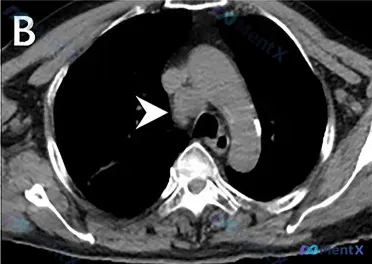

整理了一个很有警示意义的病例资料,结合影像和临床分析说一下思路: 病例核心线索 - PET/CT:延迟显像纵隔见高代谢灶,SUVmax 7.0 - 胸部CT(纵隔窗):右侧气管旁(2R/4R组区域)类圆形/分叶状软组织密度团块,边界清,密度均匀,未见钙化或中心坏死;病灶推压周围结构(主动脉弓、气管)...